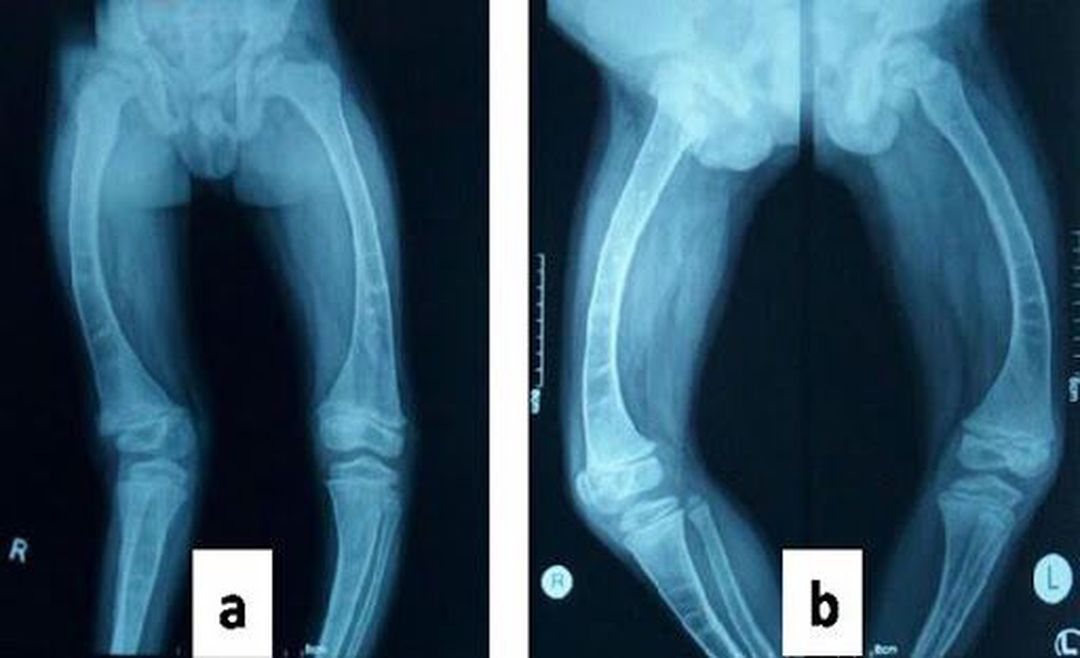

Genu Valgum / Genu Varum

Xray

Bones

Orthopedics

Deformity